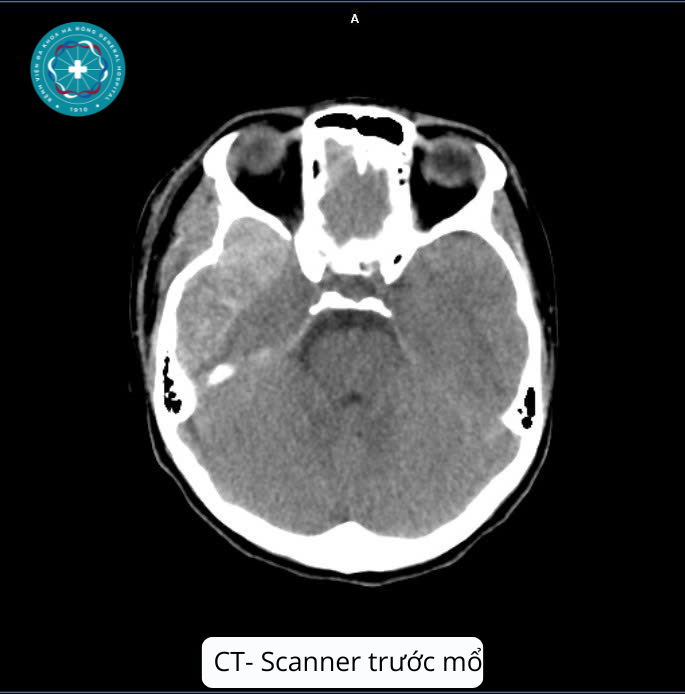

- Qua thăm khám lâm sàng và hình ảnh chụp CT-Scanner sọ não, các bác sĩ phát hiện khối Máu tụ ngoài màng cứng vùng thái dương đỉnh trái với kích thước rất lớn (78x16x82 mm), kèm tụ khí nội sọ, vỡ xương thái dương trái.

Xác định đây là trường hợp máu tụ kích thước lớn đe dọa trực tiếp đến tính mạng bệnh nhân, kíp trực Ngoại Thần kinh cùng kíp Gây mê hồi sức đã nhanh chóng tiến hành mổ cấp cứu tối khẩn cấp:

Không phải trường hợp máu tụ ngoài màng cứng cấp tính nào cũng phải phẫu thuật, dựa trên hình ảnh chụp CT-Scanner sọ não, các bác sĩ sẽ chỉ định mổ cấp cứu khi khối máu tụ có thể tích khối máu tụ >30 cm3 hoặc bề dày khối máu tụ >15mm, đè đẩy đường giữa > 5mm hoặc khi tri giác bệnh nhân giảm nhanh.